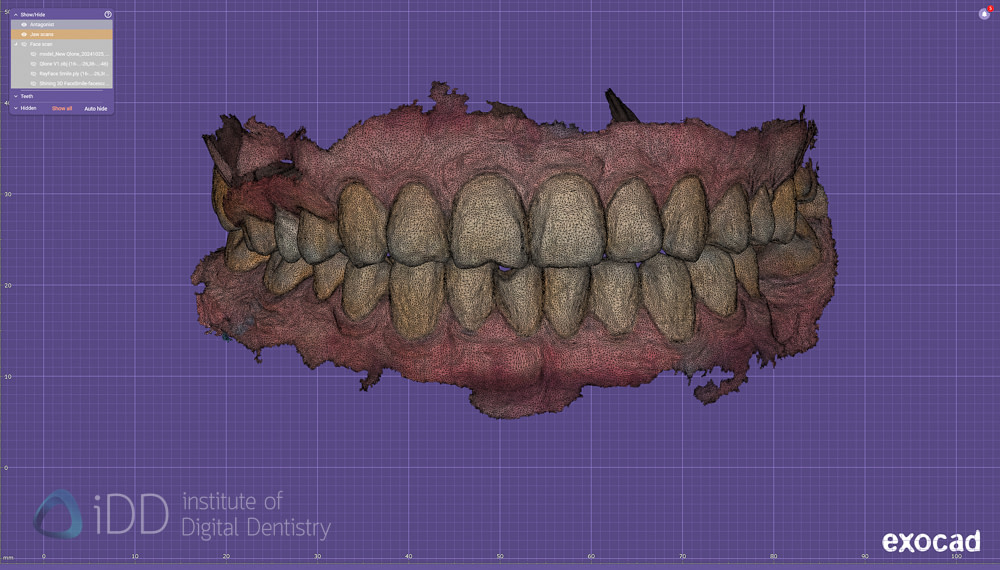

Comparing Face Scanners in exocad.

So after taking face scans with RayFace, Metismile, Qlone (original) and Qlone Dental Pro app, I brought them all into exocad to compare 2 main things - one, are there many differences between the scanners and two, how easy is it to align with IOS (the most important thing).

Qlone Dental Pro

First thing is first - you can immediately notice the texture (colour) difference between them all. Each algorithm will work differently and interestingly there is a difference between the new Qlone app and the old Qlone app - albeit slight.

As mentioned above, the colour doesn't mean a lot at all. These scans only serve a purpose if we can align IOS with them, so we must disable colors and examine the definition on the teeth - as aligning IOS and face scans is similar to aligning any other data sets in digital dentistry - by identifying common points in both.

Qlone Dental Pro

Also note the distortion in the face scanning with iPhone apps. It is interesting to see how the edges of the teeth are not exactly perfect. How much does this impact the alignment of IOS? Let's check without colour.

Qlone Dental Pro

In saying that, the new Qlone Dental Pro is a big improvement no doubt. So these are not just marketing claims. The new app really does capture the teeth and lips to a higher detail - but this cannot be thanks to hardware as I am using the same phone - it must be just smarter algorithms.

Although with the new app there is much more detail to be seen, the question is - does this look like the patient's actual teeth?

Qlone Dental Pro

The new Qlone Dental Pro was much better than the original Qlone. But again, not perfect. It is not better than Metismile nor Rayface. No way. But it is a lot cheaper, a fraction of the cost, and that may be enough to choose it over the others.

Quite good images taken with the Qlone Dental Pro. Much better when the cheeks are retracted.